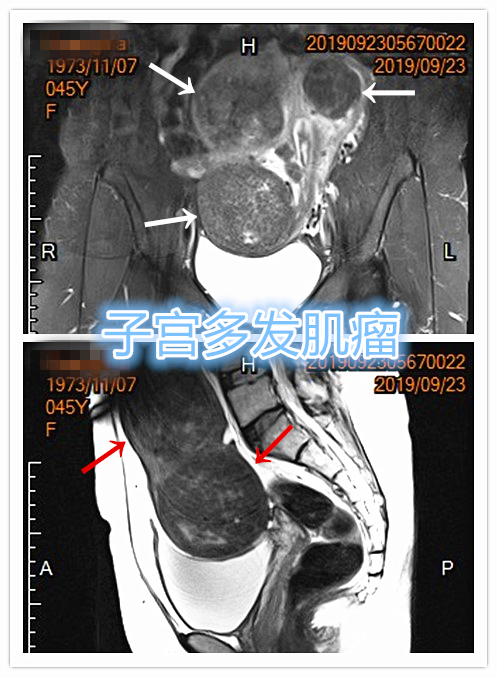

子宫多发肌瘤示意图

- MRI检查显示子宫多发肌瘤。

MRI检查示肌壁间型子宫肌瘤